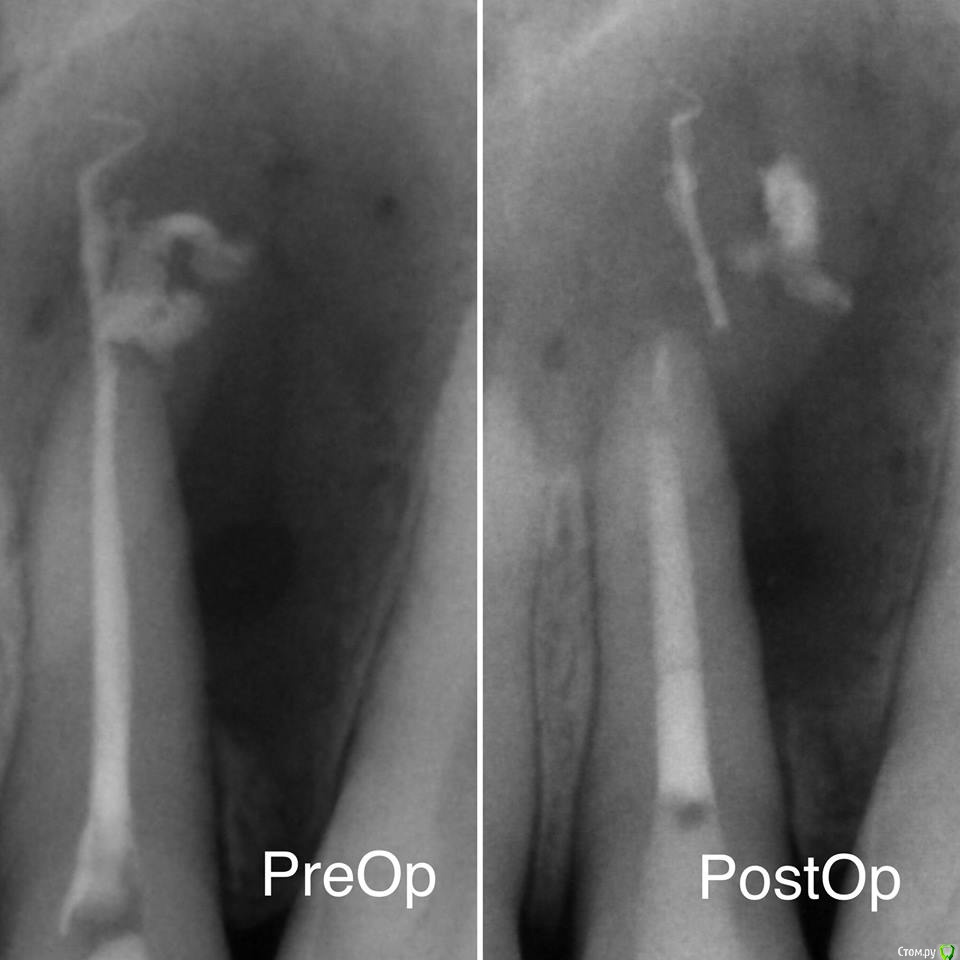

red_butler Опубликовано 22 декабря, 2017 Поделиться Опубликовано 22 декабря, 2017 25 зуб. имхо, причинный 2.4 3 Ссылка на комментарий

vse32 Опубликовано 22 декабря, 2017 Поделиться Опубликовано 22 декабря, 2017 имхо, причинный 2.4 Смотрите внимательнее контур кисты. Он же как нимб вокруг 25. Ссылка на комментарий

red_butler Опубликовано 22 декабря, 2017 Поделиться Опубликовано 22 декабря, 2017 Смотрите внимательнее контур кисты. Он же как нимб вокруг 25. У 2.5 сохранена периодонтальная щель, у 2.4 нет Ссылка на комментарий

vse32 Опубликовано 22 декабря, 2017 Поделиться Опубликовано 22 декабря, 2017 У 2.5 сохранена периодонтальная щель, у 2.4 нет Если не затруднит, нарисуйте как видите контур кисты.Если проблемный 24, то там может и эндодонтии хватит. Каналы не "айс". Ссылка на комментарий

red_butler Опубликовано 22 декабря, 2017 Поделиться Опубликовано 22 декабря, 2017 Если не затруднит, нарисуйте как видите контур кисты.Если проблемный 24, то там может и эндодонтии хватит. Каналы не "айс". 2 Ссылка на комментарий